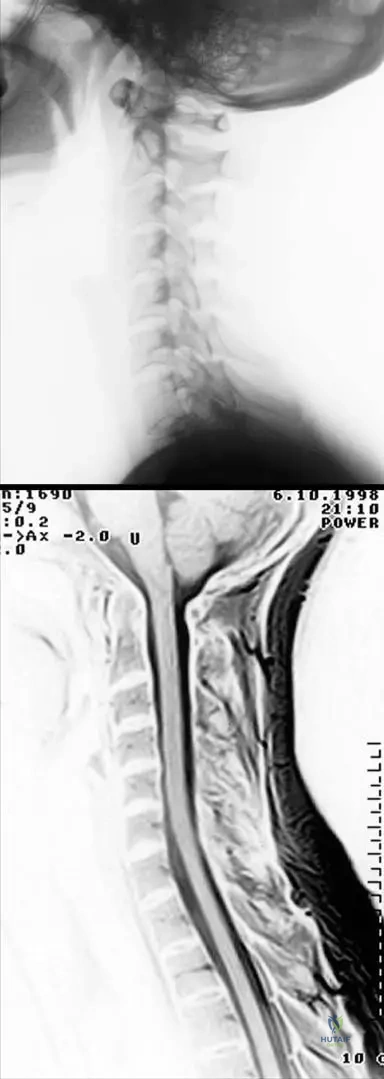

A 48-year-old female with early-stage rheumatoid arthritis reports mild neck stiffness. An X-ray and MRI of the cervical spine are performed. The images show incipient atlanto-axial synovitis with moderate subluxation, but the MRI confirms a normal liquor space around the spinal cord without cord involvement.

View Answer & Explanation

Correct Answer: D

Rationale: Even in early RA, atlanto-axial synovitis and moderate subluxation can occur. Given that the liquor space is normal and there is no cord involvement, immediate surgery is not indicated. However, the potential for progression to severe subluxation and cord compression necessitates close monitoring. The main distractor, A, is incorrect because surgical indication is typically based on severe subluxation (e.g., posterior atlantodental interval <14mm) or neurological signs, neither of which are present here.

Question 79

A 72-year-old male with severe, late-stage rheumatoid arthritis presents with progressive gait disturbance and upper extremity weakness. MRI of the cervical spine reveals severe atlanto-axial subluxation with dorsal and cranial displacement of the dens, resulting in spinal cord compression. The distance between the posterior wall of the dens and the anterior wall of the posterior arch of the atlas measures 12 mm.

Correct Answer: C

Rationale: In late-stage RA, severe atlanto-axial subluxation can lead to spinal cord compression, which is a life-threatening complication. The text explicitly states that when the distance between the posterior wall of the dens and the anterior wall of the posterior arch of the atlas is 14 mm or less, surgical indication is established regardless of neurological signs. This patient's measurement of 12 mm falls within this critical range. Neurological signs are generally not reversible. The main distractor, A, is incorrect as conservative management is insufficient for severe subluxation with cord compression and a critical measurement.